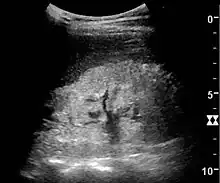

One of the primary indications for referral to US evaluation of the kidneys is evaluation of the urinary collecting system. Enlargement of the urinary collecting system is usually related to urinary obstruction and can include the pelvis, the calyces and the ureter. Hydronephrosis is seen as an anechoic fluid-filled interconnected space with enhancement within the renal sinus, and normally, the dilated pelvis can be differentiated from the dilated calyces.[1]

The hydronephrosis is typically graded visually and can be divided into five categories going from a slight expansion of the renal pelvis to end-stage hydronephrosis with cortical thinning (Figure 15). The evaluation of hydronephrosis can also include measures of calyces at the level of the neck in the longitudinal scan plane, of the dilated renal pelvis in the transverse scan plane and the cortical thickness, as explained previously (Figure 16 and Figure 17).[1]

If the fluid in the dilated collecting system has echoes, pyonephrosis should be excluded by clinical exam, blood analysis and, in special cases, puncture or drainage. Hydronephrosis can also be caused by non-obstructive conditions, such as brisk diuresis in patients treated with diuretics, in pregnant women and in children with vesicoureteral reflux.[1]